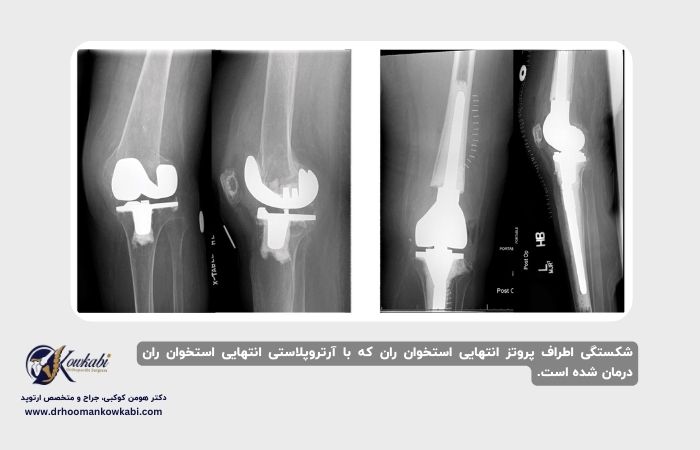

تعویض مجدد مفصل زانو

در برخی موارد شکستگیهای پریپروستتیک تعویض کامل زانو، ایمپلنت شل است. در این موقعیتها، ایمپلنت اصلی باید از استخوان خارج شود و با ایمپلنت جدید جایگزین شود. این تجدیدنظر نامیده میشود.

به دلیل از دست دادن احتمالی استخوان، جراح ممکن است از ایمپلنتهای ویژه استفاده کند. این ایمپلنتها تمایل به بزرگتر بودن برای پایداری دارند و شامل ساقههایی برای حفاظت از استخوان ضعیفتر نزدیک مفصل زانو هستند.

اگر استخوان کافی در انتهای فمور وجود نداشته باشد، جراح شما ممکن است از نوع خاصی از ایمپلنت شناخته شده به عنوان جایگزینی دیستال فمورال استفاده کند.